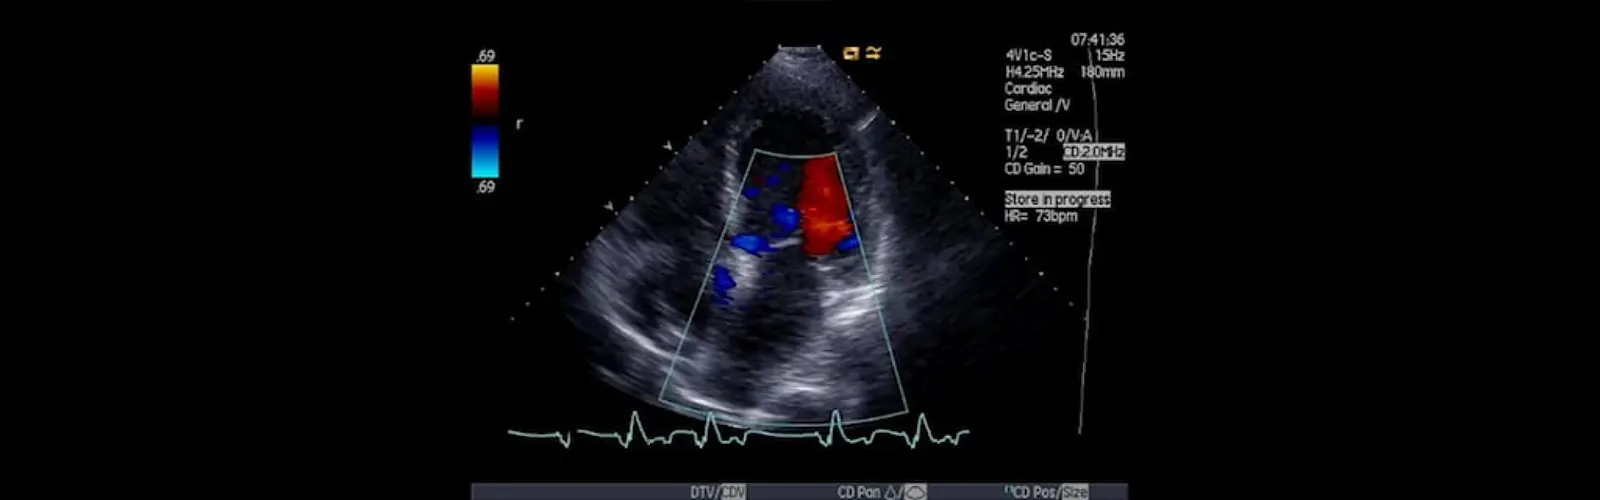

In addition to traditional ultrasound imaging, color Doppler is used to evaluate blood flow in the abdominal organs. It uses a color map to display the speed and direction of blood flow within the vessels. This information can help to identify abnormalities such as blockages, narrowing of blood vessels, or abnormal blood flow patterns.

Abdominal ultrasound with color Doppler can be used to evaluate a wide range of abdominal conditions, including liver disease, gallstones, kidney disease, abdominal aortic aneurysm, and more. It is a safe, non-invasive, and painless procedure that does not use ionizing radiation and typically takes 30-60 minutes to complete.